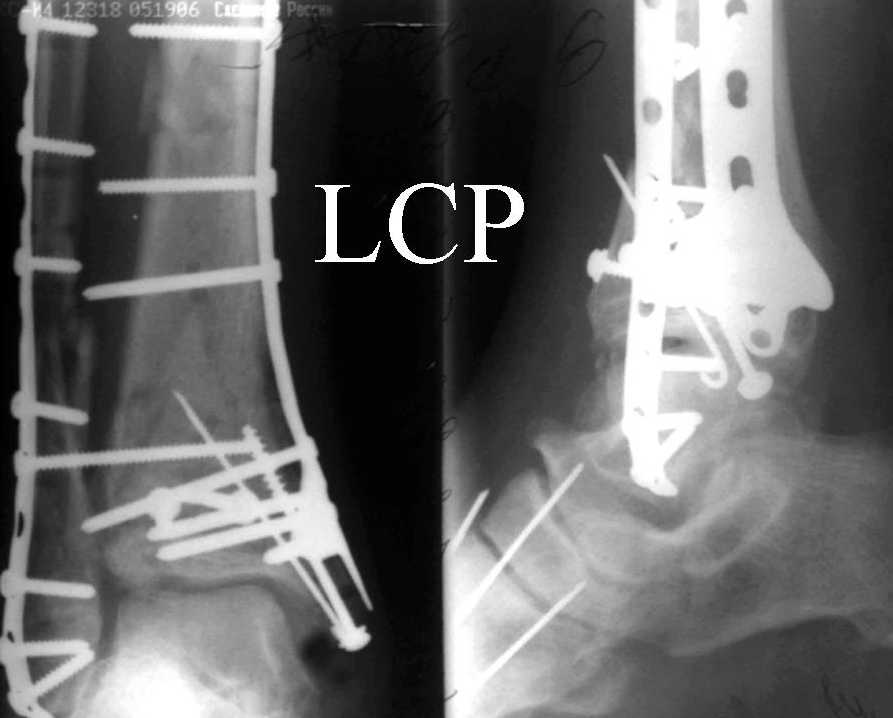

На рентгенограммах типичный перелом пилона по типу С-3. есть опыт до 100 открытых опреаций у нас в клинике. 20 примерно в год. Принцип один -все внутрисуставные переломы нуждаются в открытой репозиции и внутренней стабильной фиксации. При поступлении КТ не надо, так как получается только нагромождение костей. Истинной картины нет. Главное восстановить длину малоберцовой кости - это ключ к успеху. При поступлении меньше всего надо думать о сосудистых расстройствах, т.к. сама операция и репозиция даже сначала частичная даёт улучшение сосудитых нарушений. Причём очень быстро. Операция в 2этапа. При поступлении доступ позади наружной лодыжки, причём обязательно. После этого репозиция малоберцовой кости и фиксация пластиной 1/3 трубки под винт 3,5. Дренаж и любой аппарат наружной фиксации. Затем после спадения отёка на 5-7-10 день аппрат снимается и дугообразный разрез спереди от медиальной лодыжки 10-12 см. Главной чтобы расстояние между 1 и вторым разрезом было не меньше 7-8 см. Тогда не будет некрозов лоскутов. Таранная кость используется как матрица на неё укладываются отломки и фиксируются пицами. Ренг-контроль. Отломки лежат все отдельно, но ничего не высыпется. При переломах С-3 всегда нужна костная пластика (из крыла). Фиксация пластиной лист клевера простой или LCP. Гипс не нужен. Дренаж до 48 часов. Операция длится 3-4 часа обязательно без жгута. Посылаю примерно такой же случай.

Ja operiroval bolnogo po Vashemu, hotia sam ni ochen' ubezden' v itom, t.k. bolnoi otkazalsa na proch' ot ex.fix, ja emu sdelal ORIF + Kostnia plastika, snimky prelogiottsa,

segodnia na pereviazky koza naprezena, preshlos' sdelat' nadsechky, kak bi ee nicroz ni nachilsa, vot pochemu ni lublu otkrito vmeshatsa zdes',